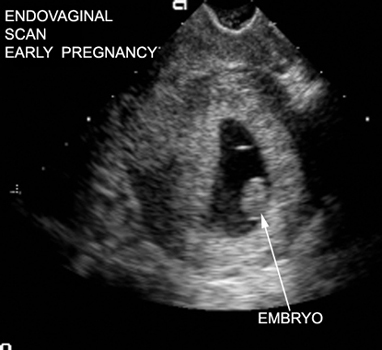

Image Atlas of Normal Pregnancy |